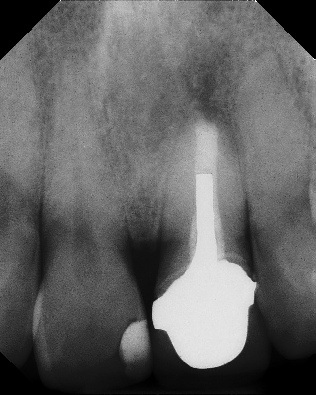

Apicoectomy - Surgical Root Canal Pre-op (post trauma) Coronal segments obturated Apical segments surgically removed 3 years